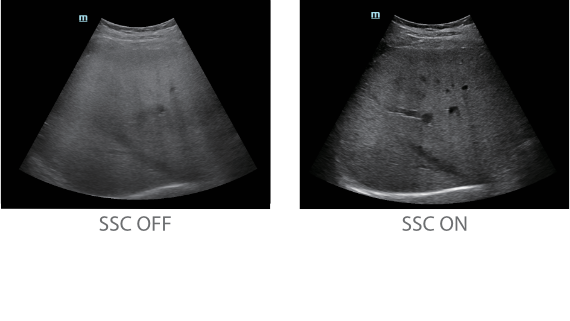

Since the company was founded, Mindray has been continuously exploring new ways to improve diagnostic confidence. Powered by the most revolutionary ZONE Sonography? Technology, Resona 7ŌĆÖs new ZST+ platform brings ultrasound image quality to a higher level by zone acquisition and channel data processing.